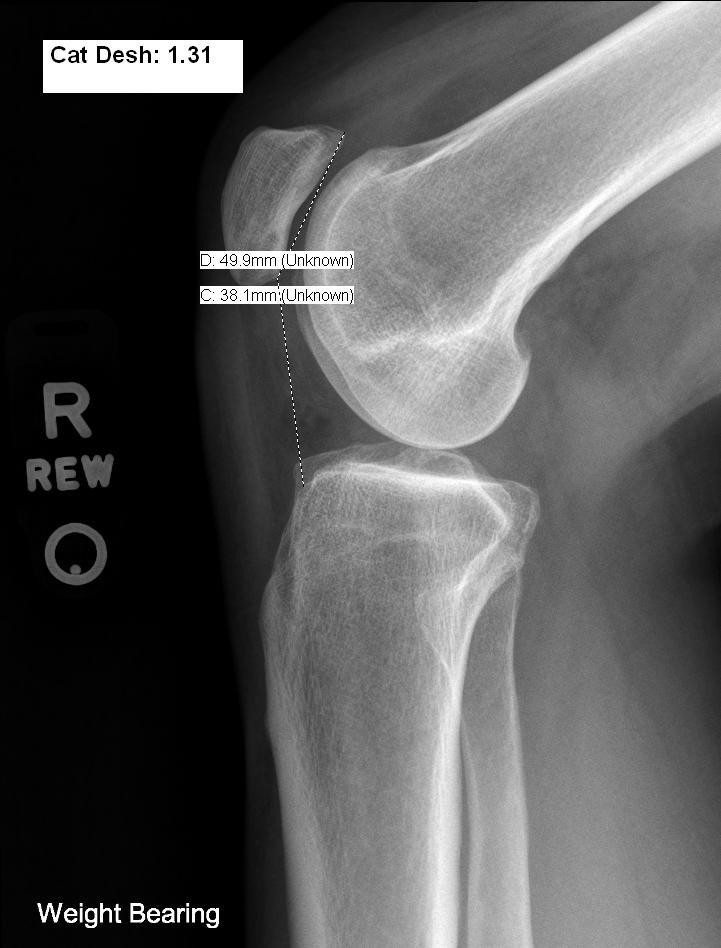

From www.ejradiology.com

Patellofemoral morphometry in patients with idiopathic patellofemoral Chondromalacia Patella X-Ray Chondromalacia patellae is a condition where there is damaged cartilage behind the patella (kneecap). It is like a softening or. In all but the most advanced cases, there is no convincing radiological change. Chondromalacia patellae is a condition characterized by softening, fraying, and ulceration of patellar articular cartilage. Softening or wearing away of the patellar articular cartilage (chondromalacia patella) causes. Chondromalacia Patella X-Ray.